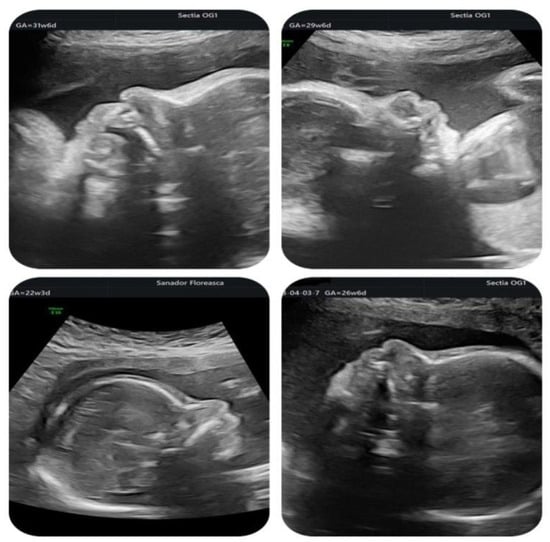

| Gestational age at cardiologic diagnosis | 22 weeks |

| Cardiologic diagnosis | IAA type B, malalignment-type VSD, pulmonary valve dyplasia, ARSA |

| Other ultrasonographic findings | Polyhydramnios Enlarged CSP Thymus hypoplasia Bulbous nose |